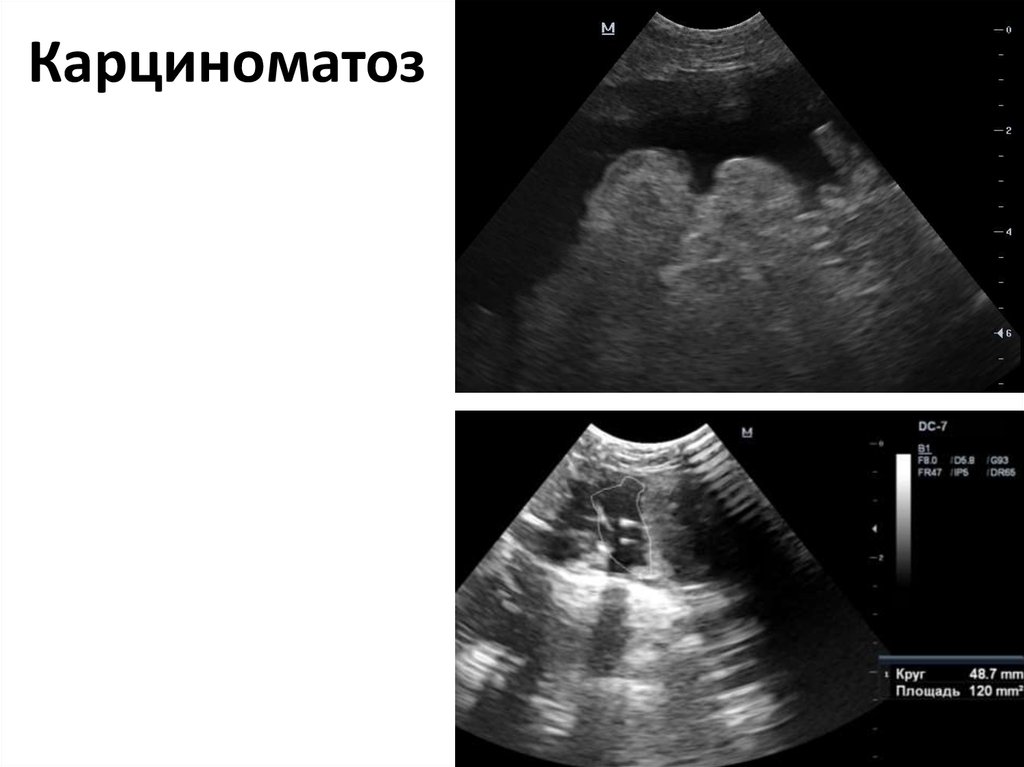

Карциноматоз